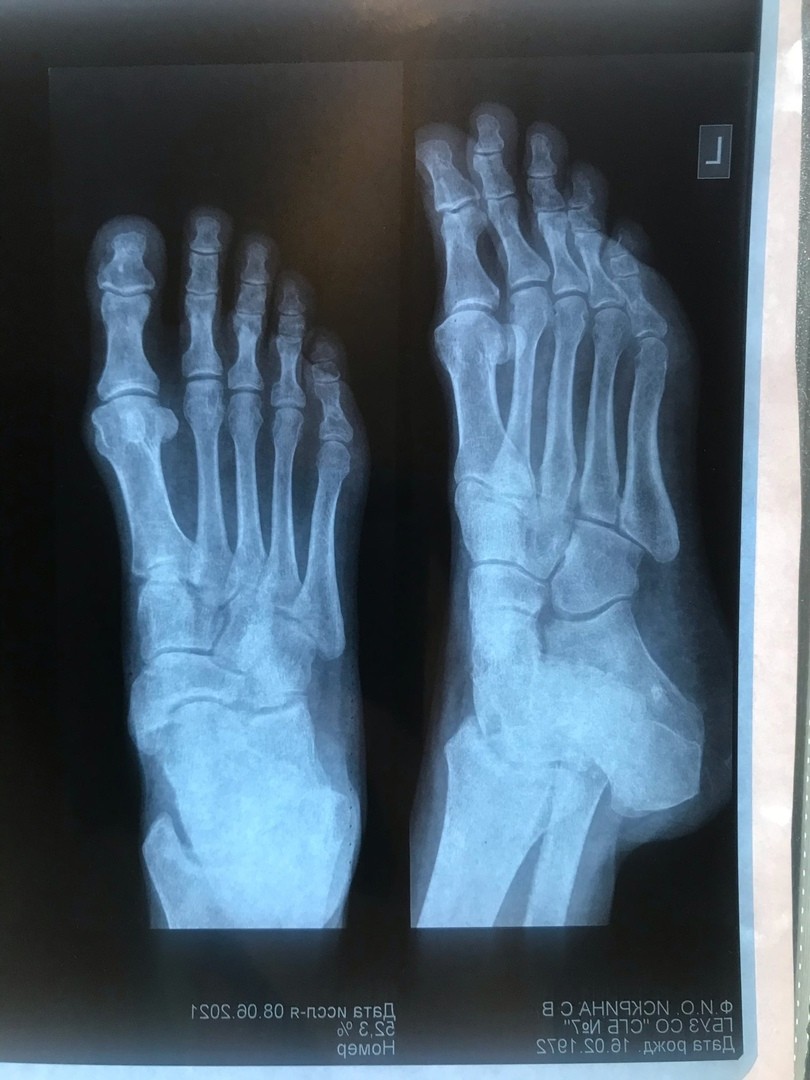

Помогите описать рентген перелома мизинца стопы

Здравствуйте, Помогите. Пожалуйста описать рентген перелома мизинца. Смещенный? Оскольчатый? Что с суставом? Прошло 2 месяца боли не прекращаются. Ходить не могу. Ночью просыпаюсь от боли. Что делать дальше после 2х месяцев? Развился артрит? Травматолог ничего по снимку не объяснил. Сказал что не оперируют только отрезают? Нужна операция? Не поздно спустя 2 месяца?

Сращения нет, смещение есть. Показано хирургическое лечение.